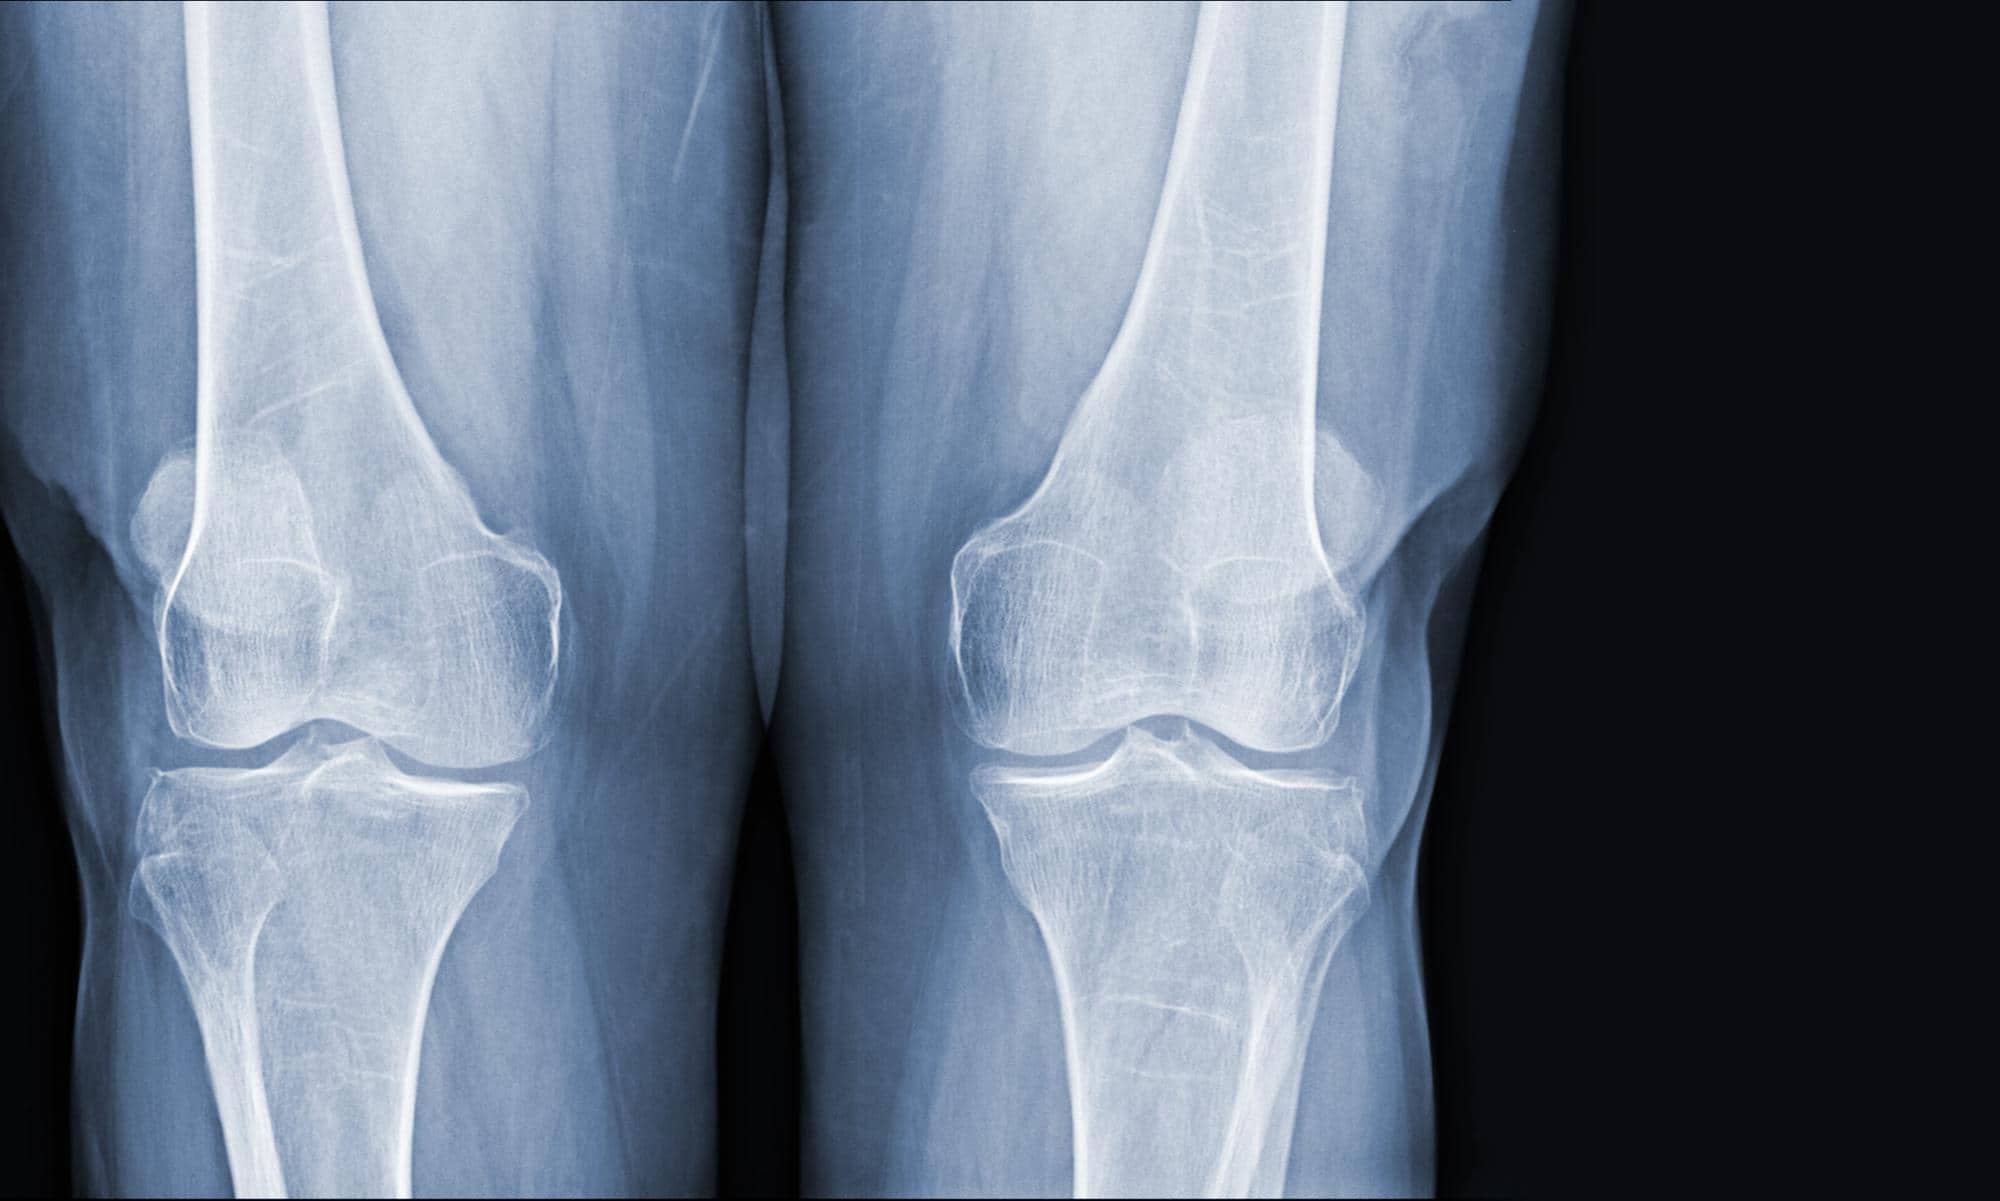

Der Schenkelhals (fachsprachlich Collum femoris) ist der knöcherne Verbindungsbereich zwischen dem Oberschenkelschaft und dem Hüftkopf. Bricht dieser Knochen, wird die Blutversorgung des Hüftkopfes unterbrochen oder stark beeinträchtigt. Verstreicht zu viel Zeit ohne operative Versorgung, kann das Knochengewebe im Hüftkopf absterben, medizinisch als Hüftkopfnekrose bezeichnet. Aus diesem Grund gilt: Ein Oberschenkelhalsbruch muss in der Regel innerhalb von 24 Stunden operativ versorgt werden.

Je nach Schwere der Fraktur und Alter des Patienten kommen unterschiedliche operative Verfahren in Betracht. Bei jüngeren Patienten wird versucht, das Gelenk zu erhalten und die Bruchstücke mit Schrauben, Nägeln oder Platten zu stabilisieren. Bei älteren Patienten, insbesondere ab dem 65. Lebensjahr, ist oft der Einsatz einer Hüfttotalendoprothese (Hüft-TEP) die Methode der Wahl, da sie die besten Heilungschancen bietet und eine schnelle Mobilisation ermöglicht. Eine konservative Behandlung, also ohne Operation, kommt nur bei stabilen, nicht verschobenen Brüchen oder bei Patienten infrage, bei denen ein chirurgischer Eingriff ein zu großes Risiko darstellt.

Diagnostische Fehler: Nicht jeder Oberschenkelhalsbruch geht mit starken Schmerzen einher. Bei stabilen oder unverschobenen Brüchen können Patienten sogar noch selbstständig gehen. Wenn ein Arzt trotzdem nach einem Sturz keinen Röntgenbefund anordnet oder einen bestehenden Bruch übersieht, liegt ein Befunderhebungsfehler vor. Dieser kann zur Hüftkopfnekrose führen, weil die dringend erforderliche operative Versorgung ausbleibt. Derartige Diagnosefehler sind in der Praxis keine Seltenheit und führen regelmäßig zu erheblichen Folgeschäden.